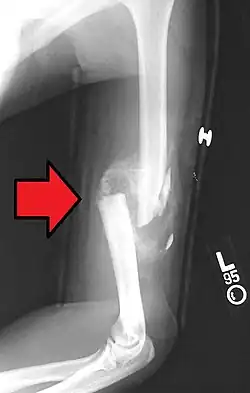

A transverse fracture of the humerus shaft